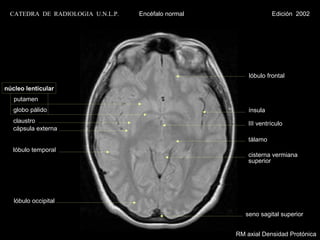

CATEDRA DE RADIOLOGIA U.N.L.P.   Encéfalo normal                Edición 2002

lóbulo frontal

núcleo lenticular

putamen

globo pálido                                         ínsula

claustro                                             III ventrículo

cápsula externa

tálamo

lóbulo temporal

cisterna vermiana

superior

lóbulo occipital

seno sagital superior

RM axial Densidad Protónica